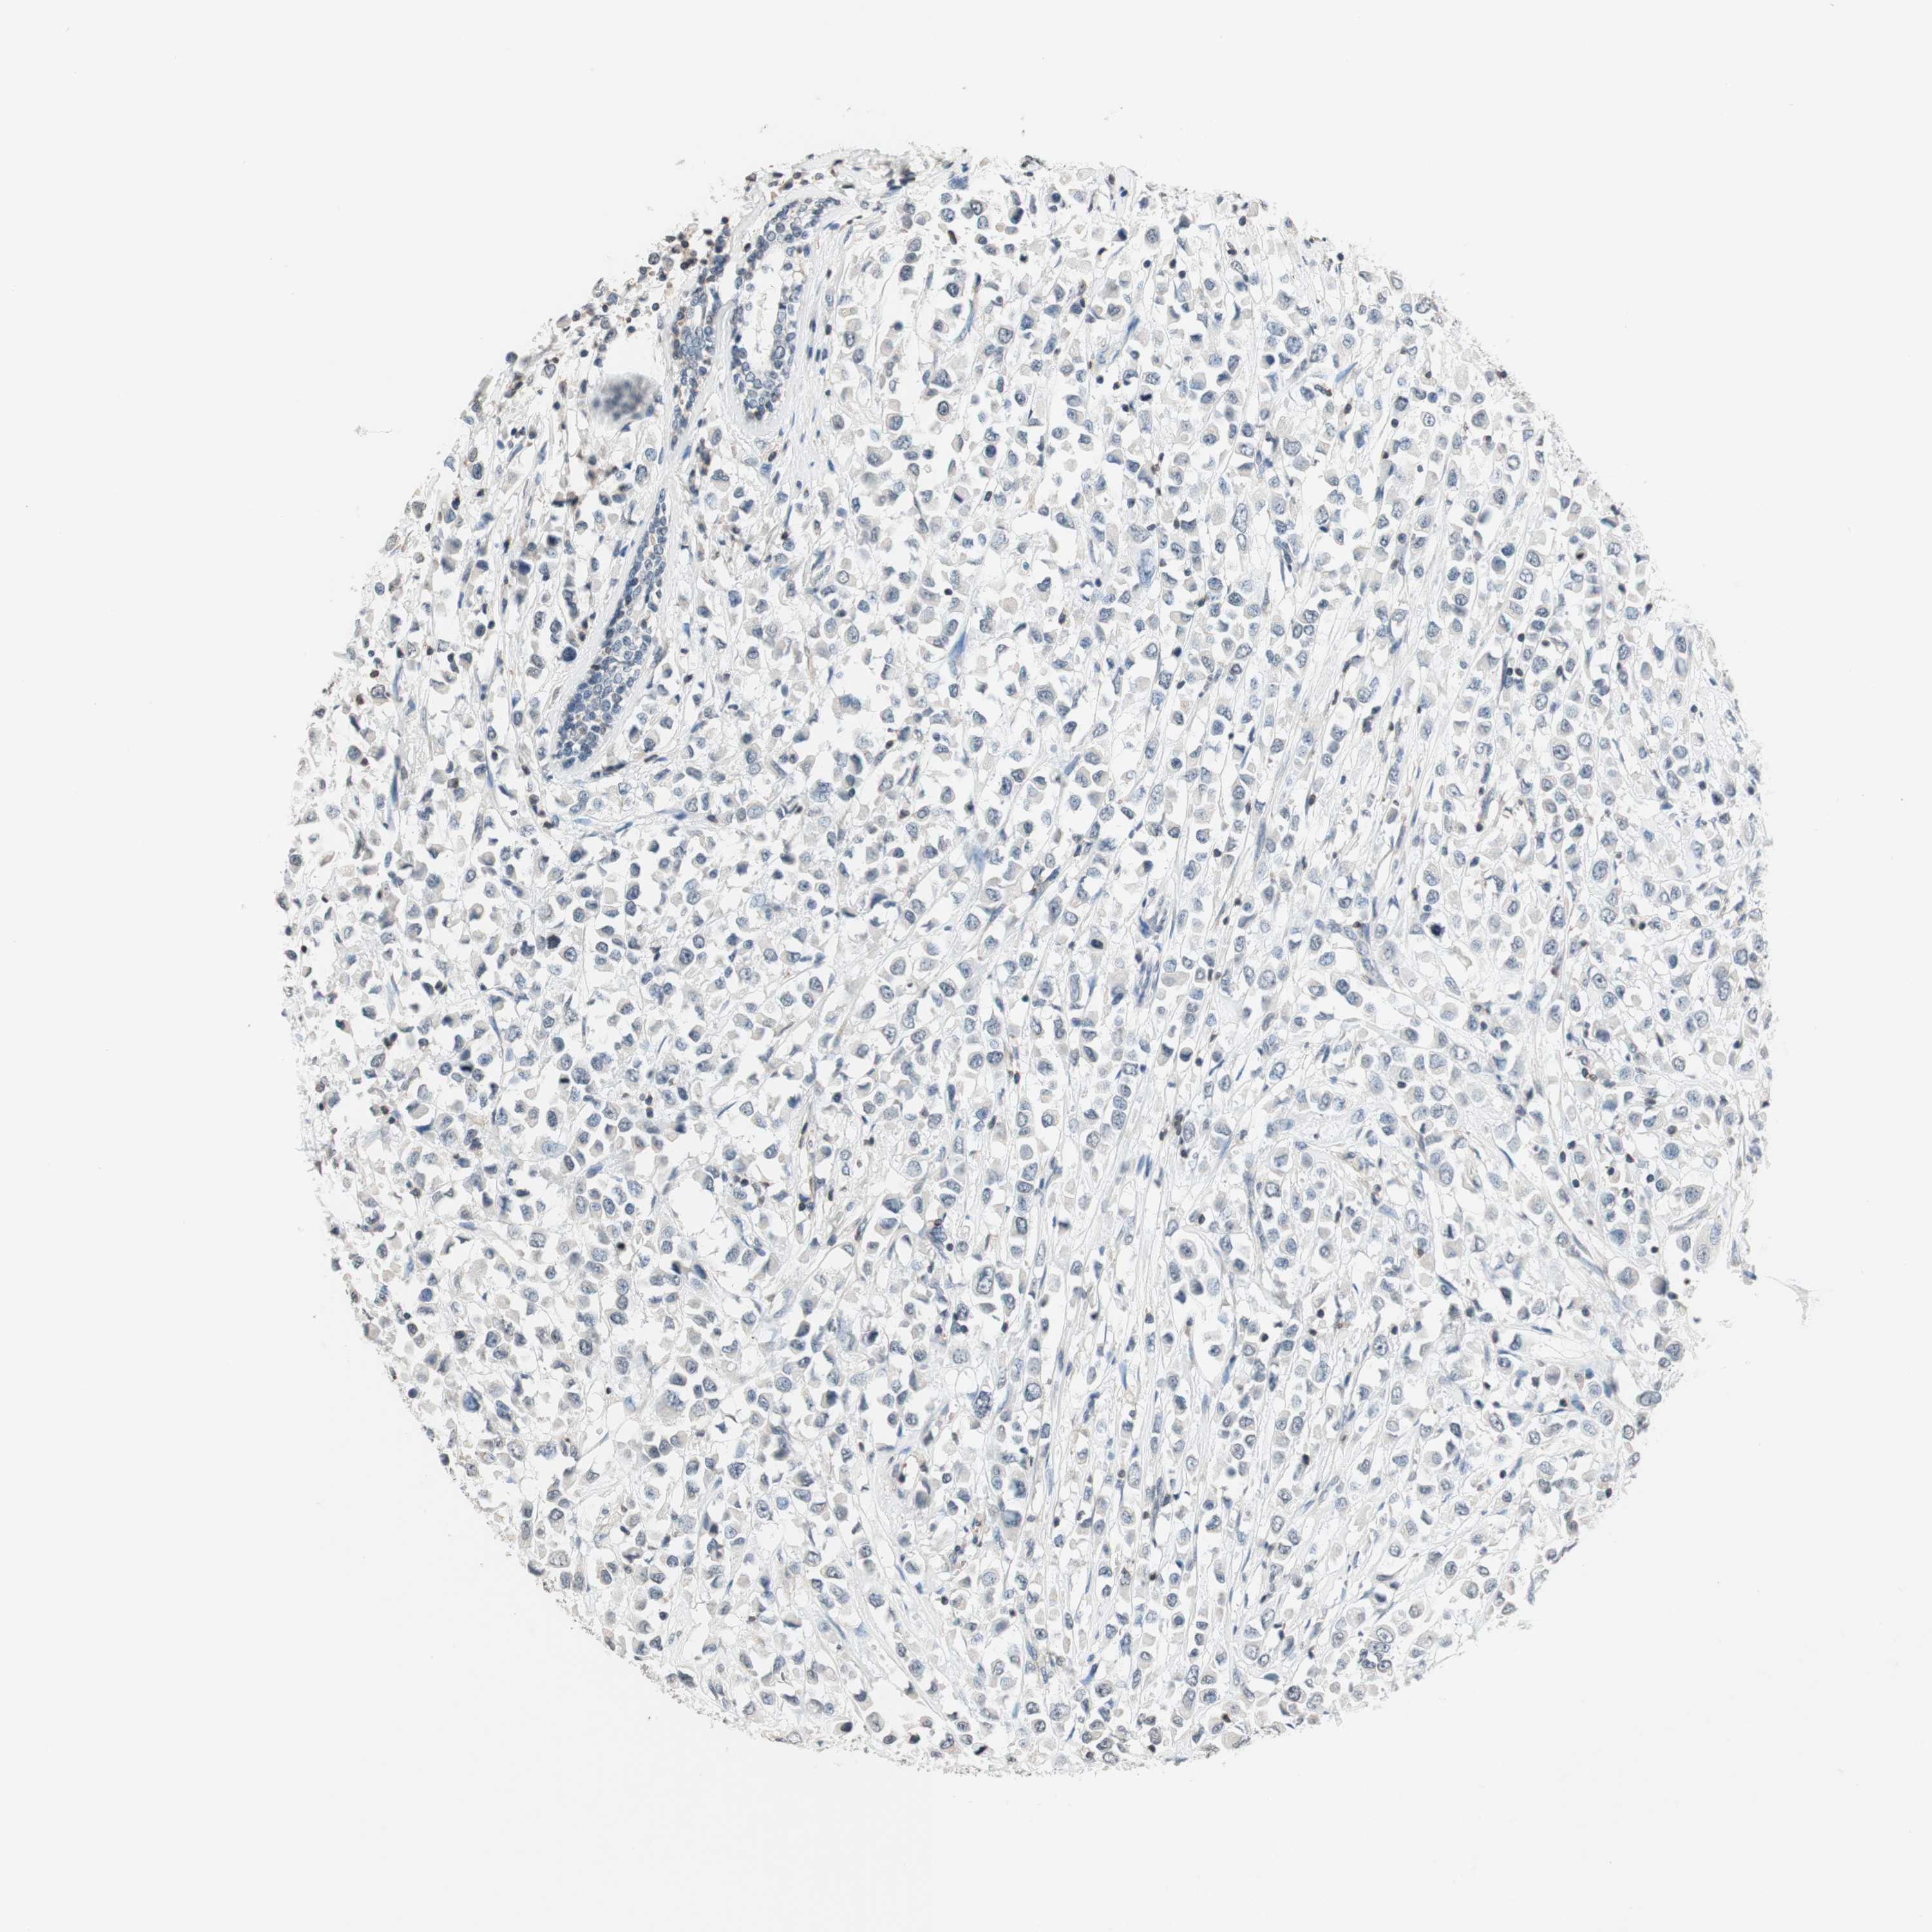

BRCA TCGA BRCA VALIDATION PROTEIN EXPRESSION

ANTIBODIES

AND

VALIDATION